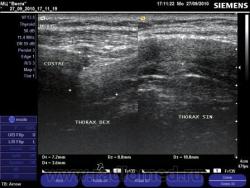

Уважаемые коллеги! Позволю себе разместить редко диагностируемую, с точки зрения доказательной медицины, травму. Перелом хрящевой части 9-10 (или совместную их часть) ребер справа. Пациент 34 года, в анамнезе травма грудной клетки. Жалобы на боль справа по реберной дуге по средне ключичной линии. При пальпации резкая болезненность и "симптом клавиши". На рентгенограммах косто-травматических изменений со стороны ребер не выявлено. На точку болезненности поставил датчик. На сонограмме справа симметричная, "здоровая" половина грудной клетки.

Видел пару раз перелом хряща на КТ. Клиника перелома ребра, на рентгенограмме всё спокойно, а на КТ выплыло.

В практической работе, часто прихидиться сталкивается с ситуацией, когда D.S.перелом хрящевой части ребра, явно напрашивается из клинических данных, но доказать это R-ски не представляется возможным. Демонстрация коллеги показывает, что перелом хрящевой части ребра, можно реально подтвердить на УЗИ линейным датчиком. Единственно, такое впечатление, что такая патолгия едва ли является редкой, хотя со мной может быть, несогласятся травматологи.